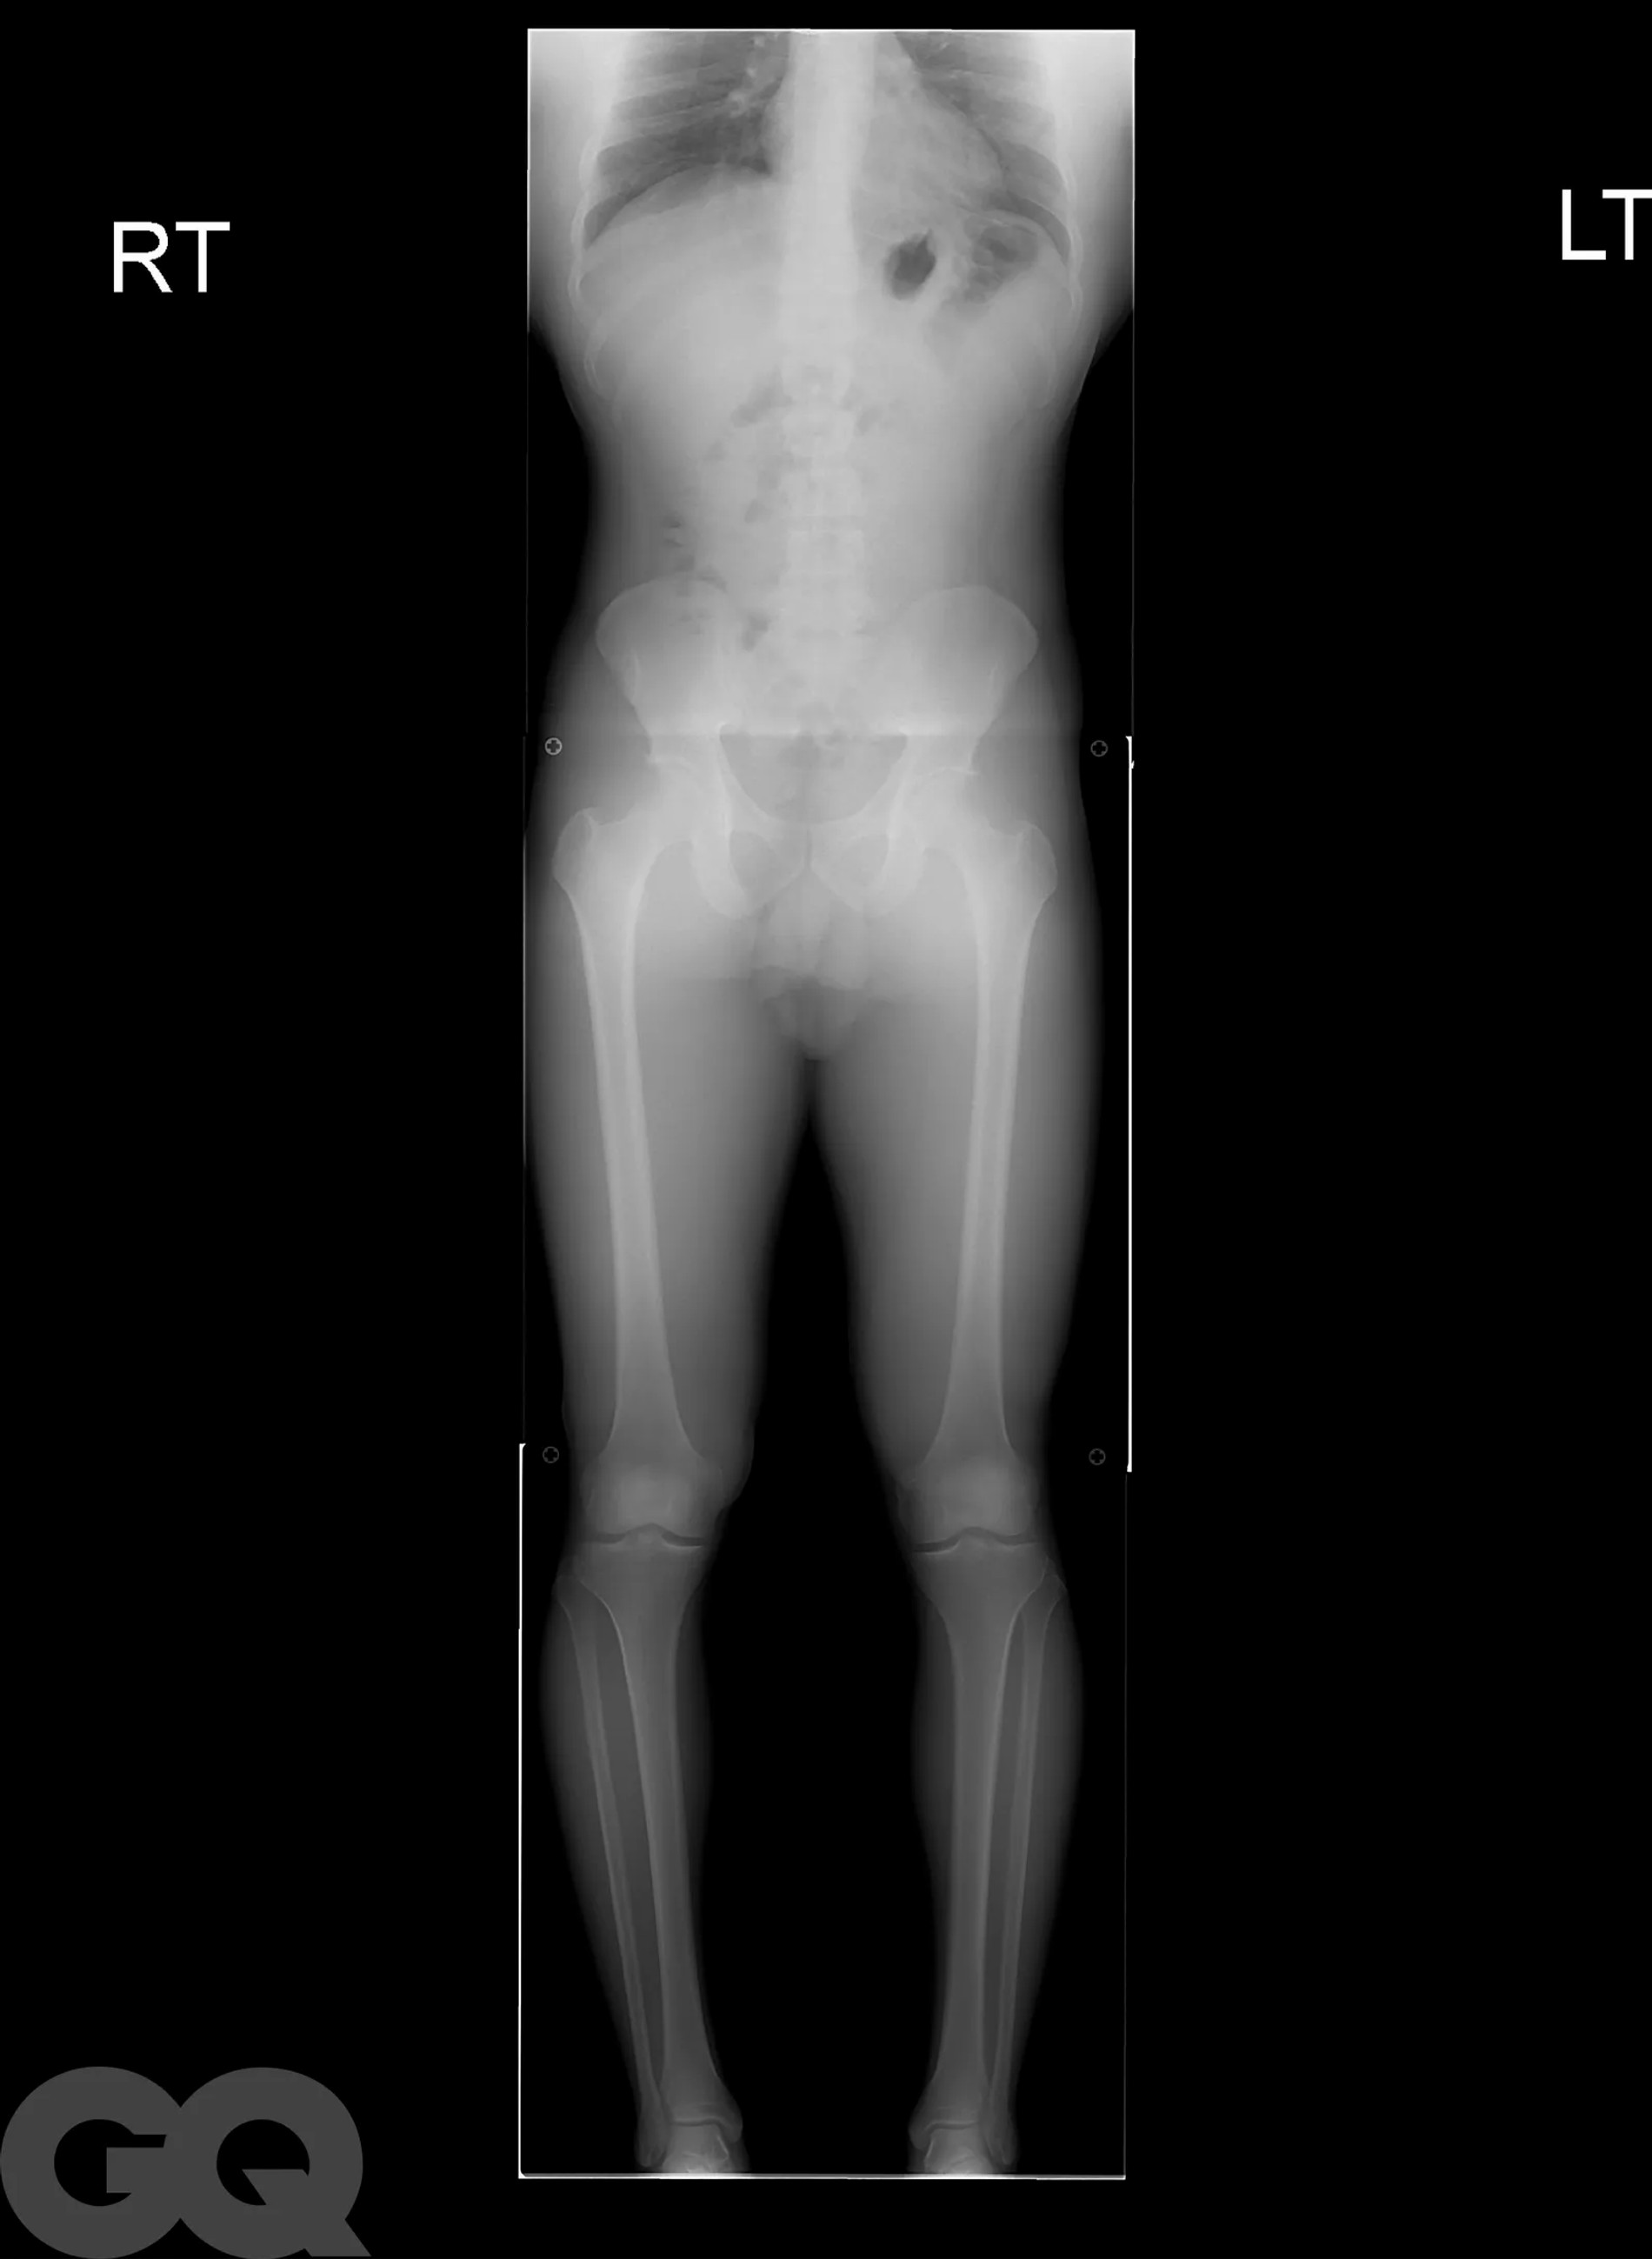

Надо сказать, что операция эта больше напоминает самую настоящую экзекуцию. Она основана на методике советского хирурга-ортопеда Гавриила Илизарова, которая изначально была разработана для пациентов со сложными переломами костей. Американские специалисты ее доработали и сделали более щадящей, но все же. В погоне за несколькими добавочными сантиметрами мужчины соглашаются на то, чтобы их собственные бедренные кости были сломаны. Да, без этого никак.

После перелома между костями вставляют регулируемые титановые стержни, которые наращивают на один миллиметр каждый день в течение примерно 90 суток с помощью магнитного пульта дистанционного управления. Как только сломанные кости срастутся, человек становится выше ростом и снова может ходить. Обычно весь процесс занимает 1 год, реабилитация сопровождается болью, что нисколько не смущает мужчин, решивших немного подрасти.